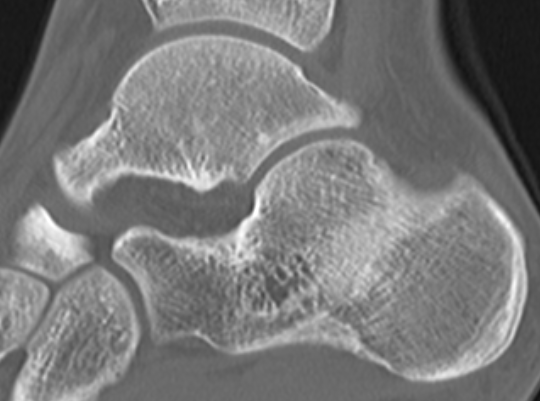

CT

TC coalition middle facet

Complete synostosis of the medial TC joint with OA of the posterior subtalar joint